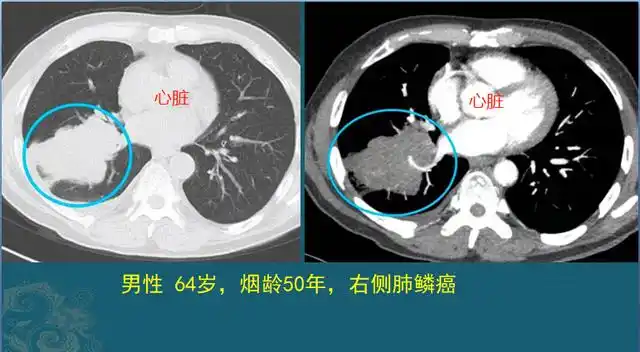

先看一张肺癌病人的ct片子,有点遗憾也有点幸运!